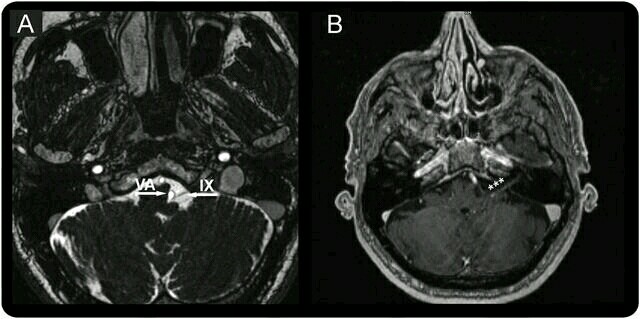

者男性,65岁,主因舌根部和左侧扁桃体窝阵发性刺痛2个月就诊,吞咽和打呵欠可加重疼痛。患者一般体格检查和神经系统体格检查均无异常。诊断为舌咽神经痛,给予奥卡西平300mg,一日3次,对症使用来缓解疼痛。 颈部MRI示左侧舌咽神经靠近椎动脉,且舌咽神经可见异常强化(如下图所示)。 异常的舌咽神经强化提示其出现炎症性改变,可能继发于动脉对神经的刺激所致。